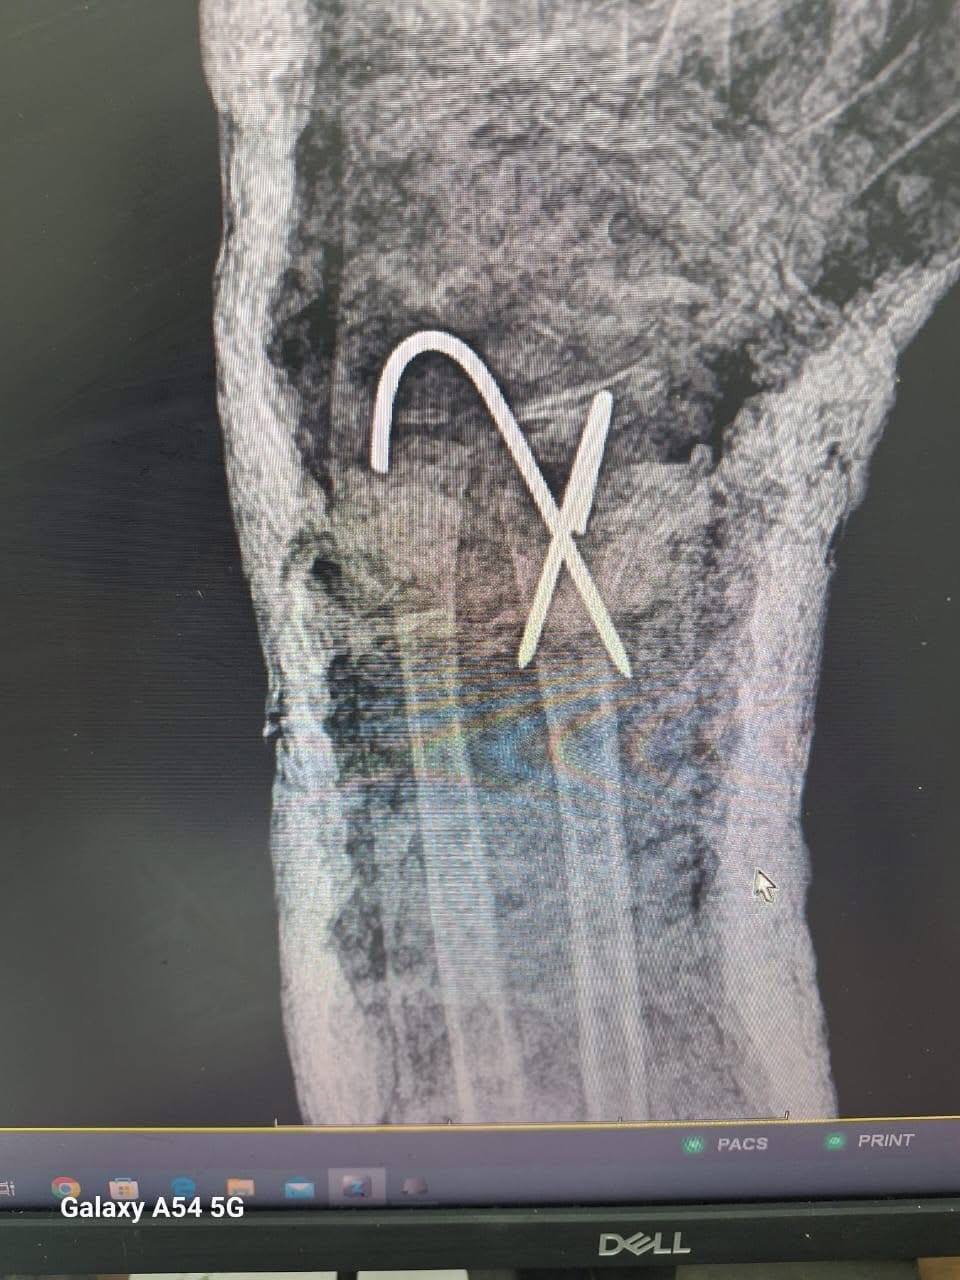

وأضاف الخضيري، أنه تم إجراء 3 عمليات بقسم الأنف والأذن، و3 عمليات بقسم العظام، بالإضافة إلى 4 عمليات جراحية متنوعة، بما يعكس جاهزية الأقسام المختلفة بالمستشفى لتقديم خدمات طبية متكاملة للمرضى